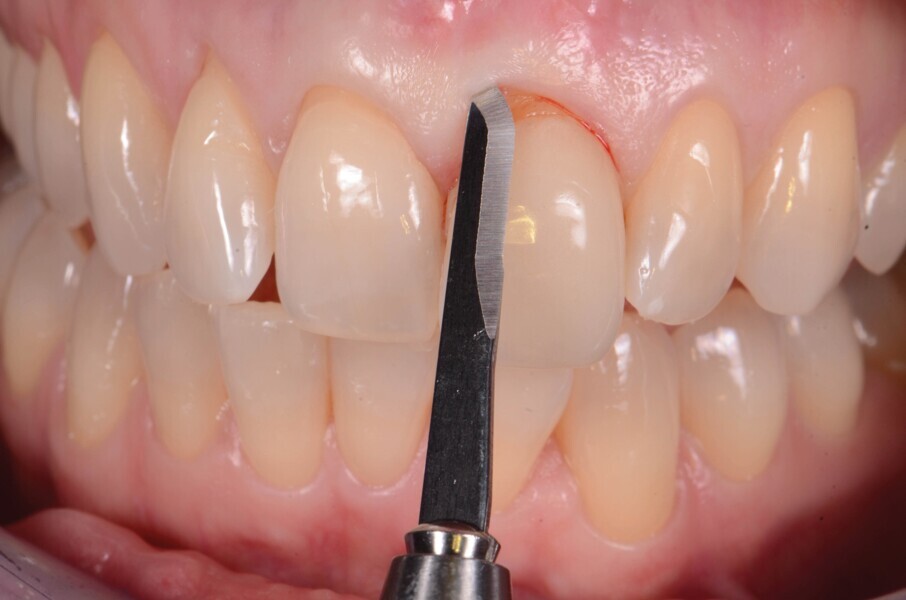

La dent 21 est extraite de la manière la moins traumatique possible à l’aide d’un périotome (Fig. 4). Elle est conservée dans du sérum physiologique afin de pouvoir l’utiliser comme restauration provisoire par la suite.

Fig. 4 : Extraction atraumatique de la dent 21.